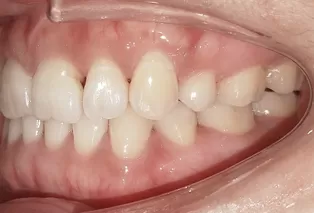

Photos intra-orales après traitement